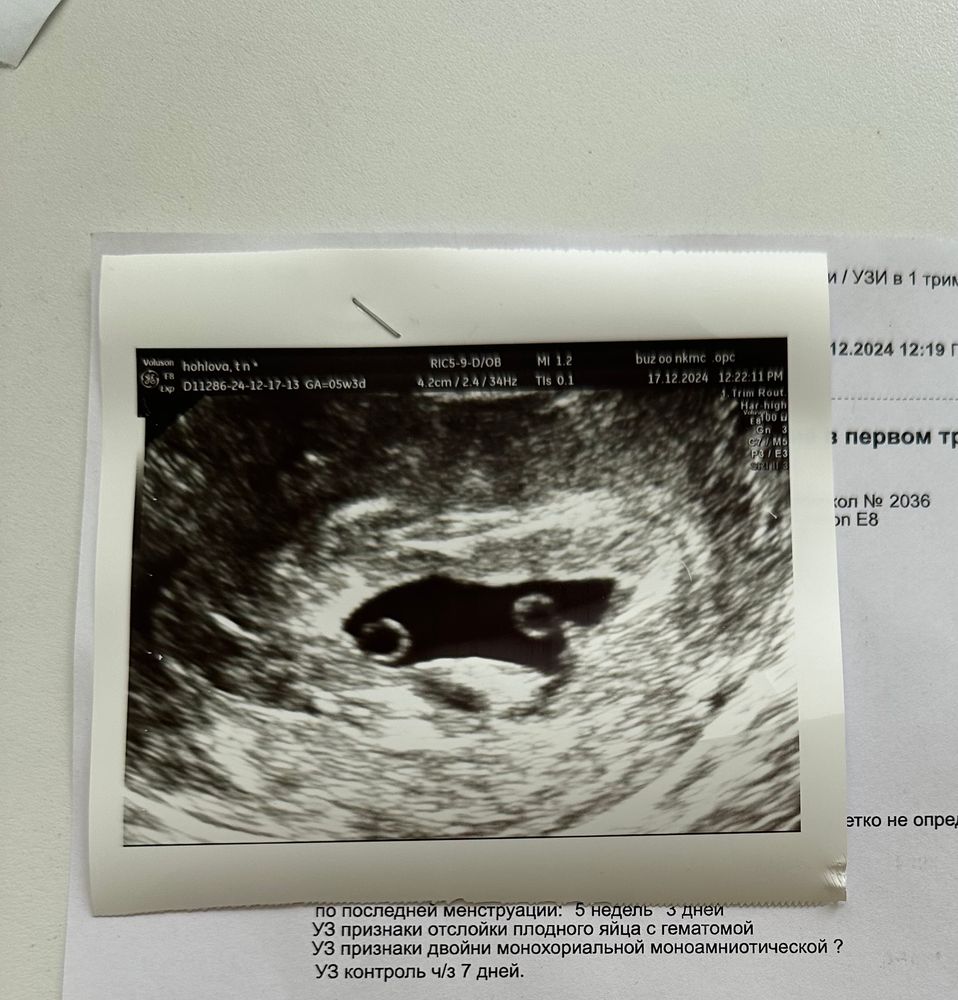

УЗИ. Одно плодное яйцо, но…

Кровотечение. Ретрохиальная гематома